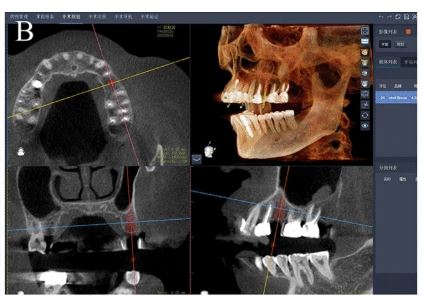

Case below by: Yang S, Chen J, Li A, Li P, Xu S. Autonomous Robotic Surgery for Immediately Loaded Implant-Supported Maxillary Full-Arch Prosthesis: A Case Report

Virtual 3D planning positions for placing six implants and four metallic pins in the maxilla. In the panoramic radiograph, red implants show a diameter of 3.4 mm, yellow implants indicate a diameter of 4.0 mm, and blue ones represent metallic pins.